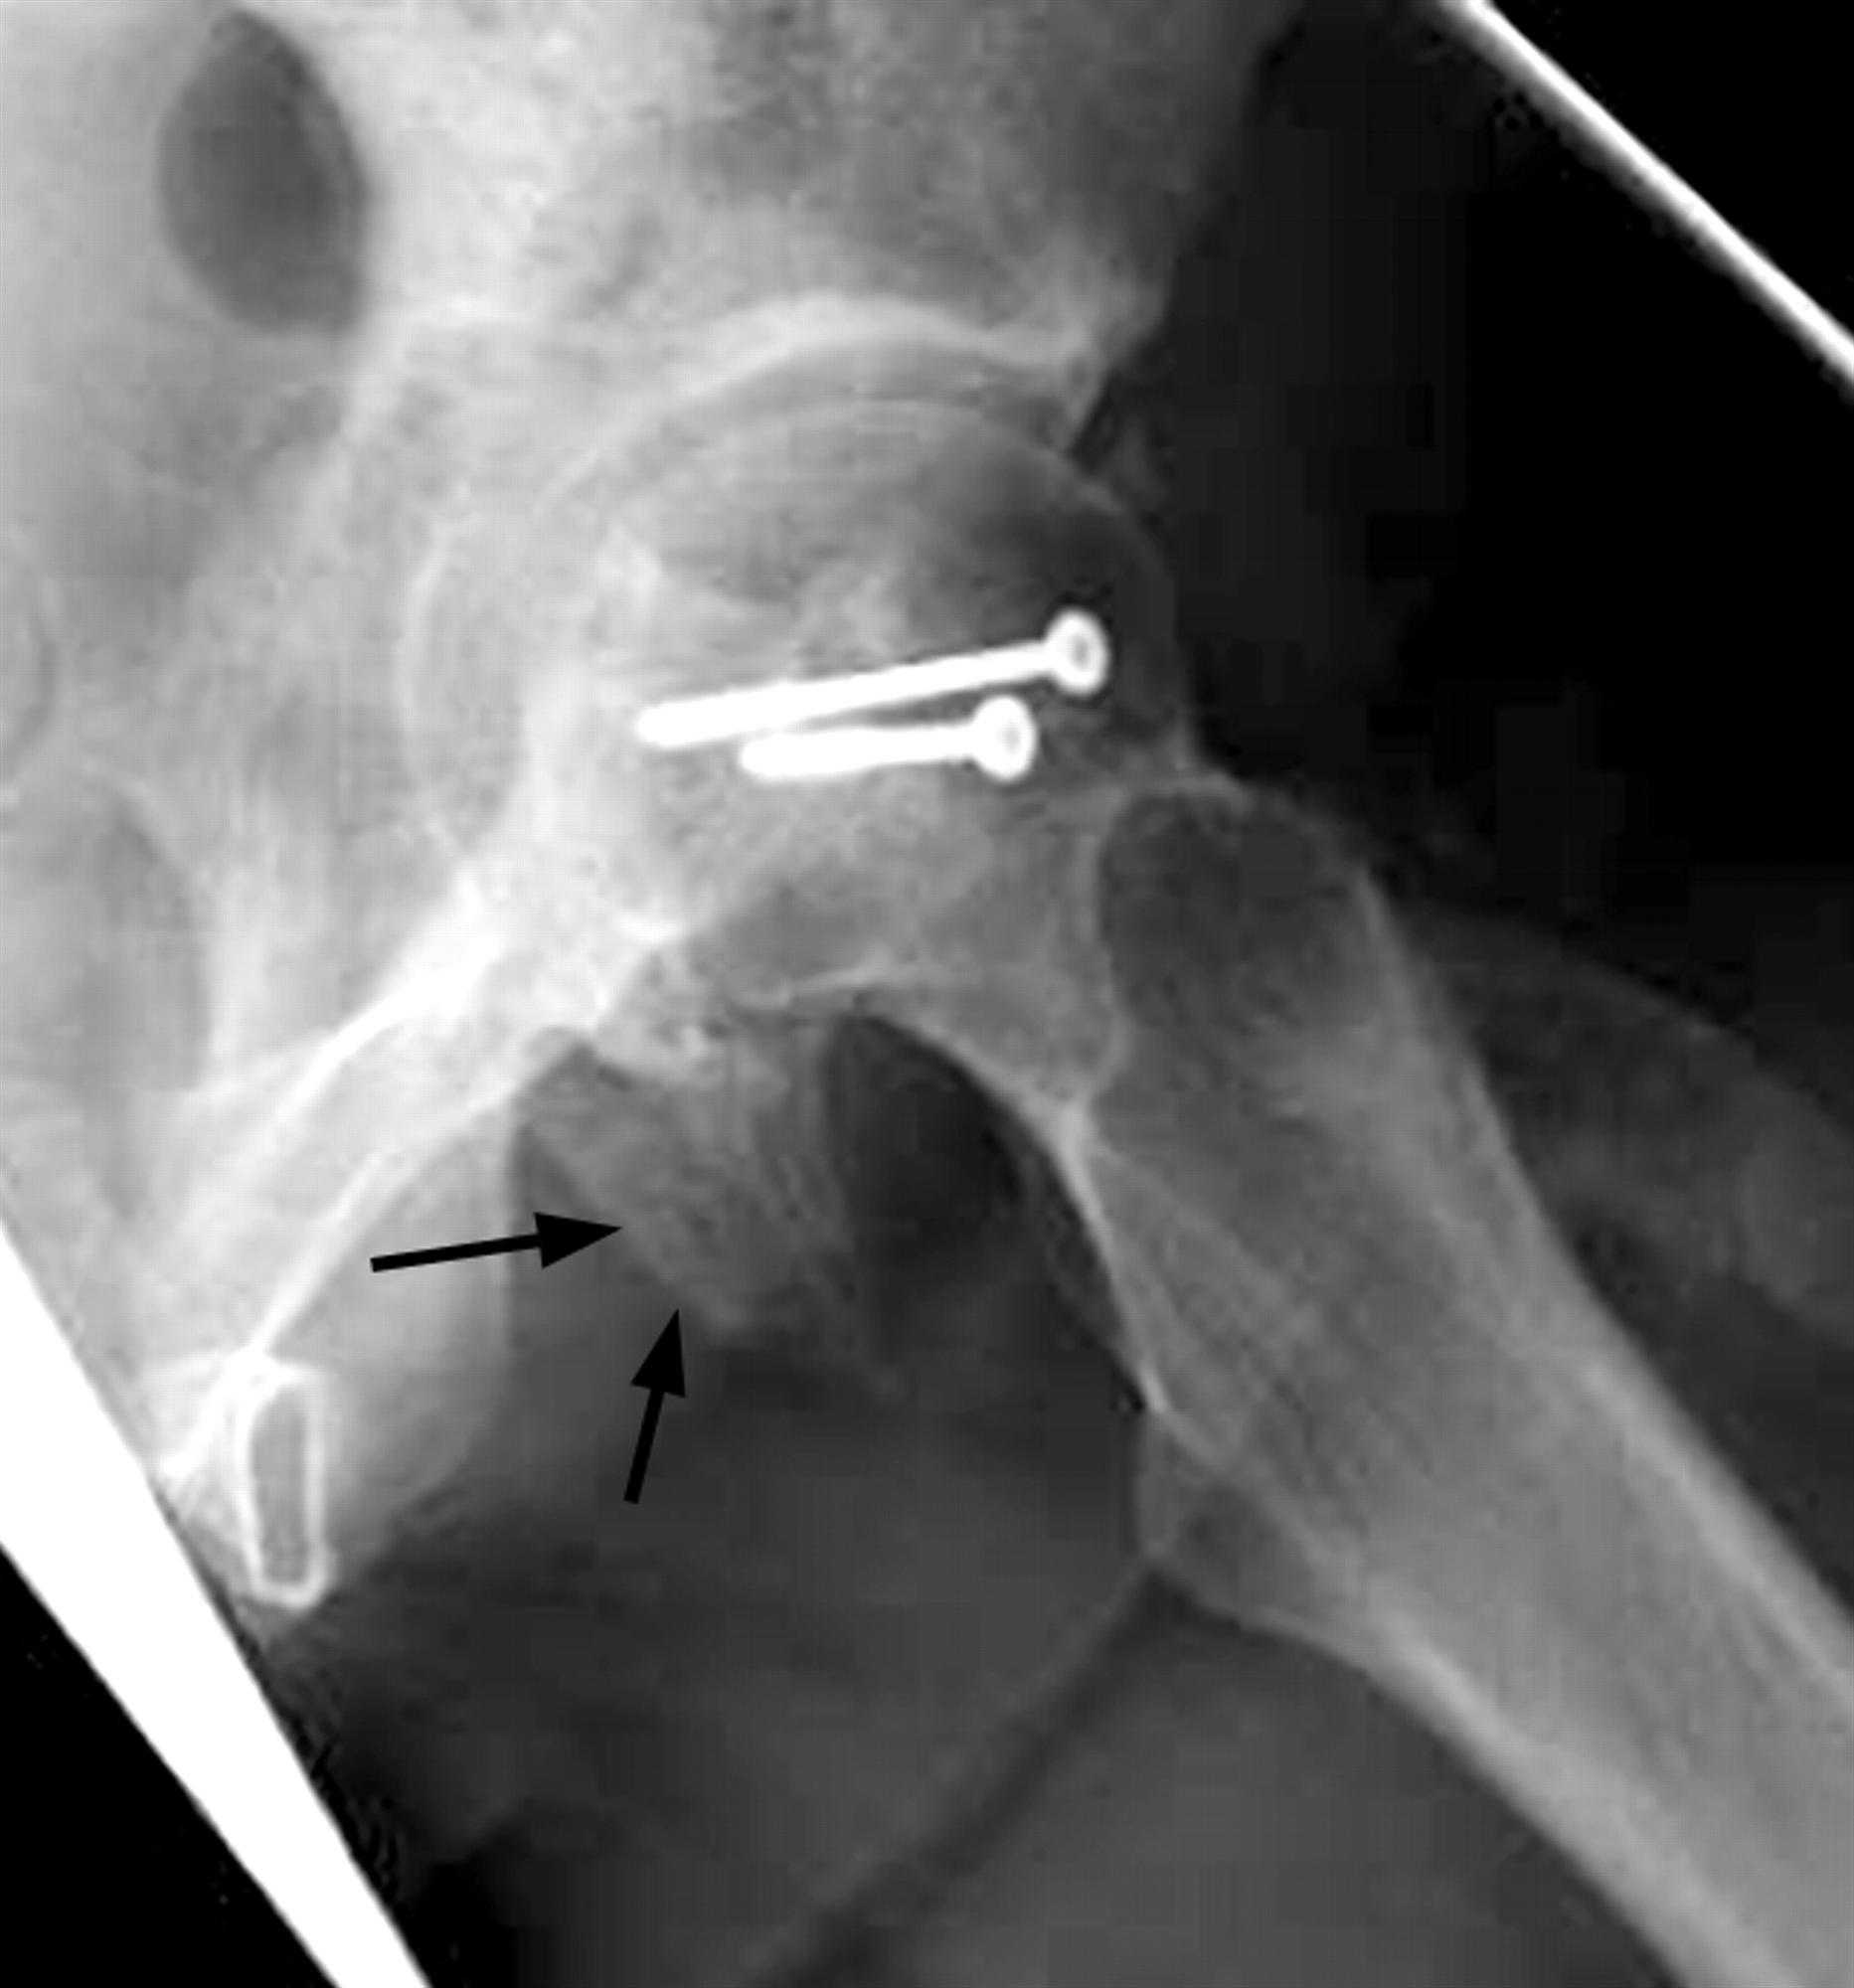

Hip Fracture (Neck of Femur / NOF) almostadoctor

Neck of femur fracture surgery wikidoc Spontaneous Femur Fracture fractures through abnormal bone are called “pathological” fractures. bisphosphonate therapy minimizes bone loss and reduces fracture risk by up to 50% in patients with osteoporosis, 1 but it is. atypical femur fracture, which is a rare type of fracture that has been. Probably the most common cause of this is an underlying. among the most common. Spontaneous Femur Fracture.

From almostadoctor.co.uk